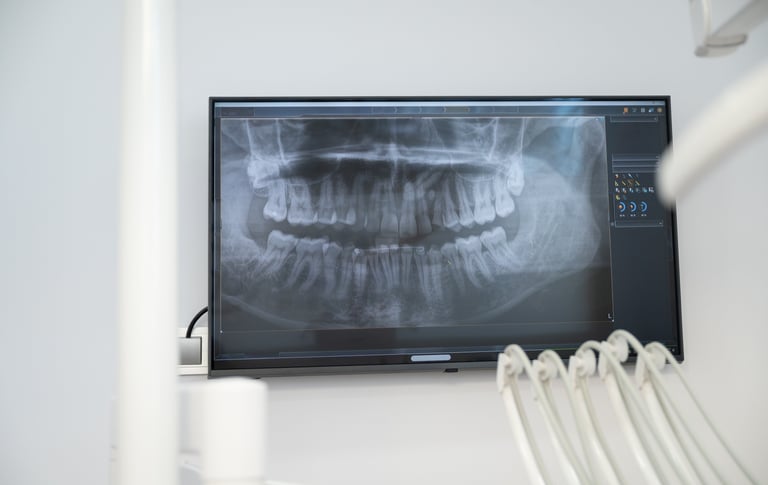

A avaliação endodôntica combina exame clínico, radiografias e análise de sintomas. Essa etapa é fundamental para identificar:

1. Diagnóstico Preciso.